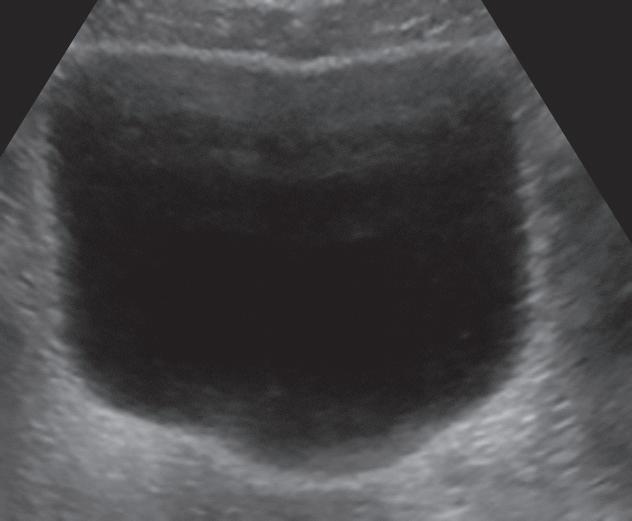

Bexiga urinária com capacidade habitual, com paredes de espessura normal.